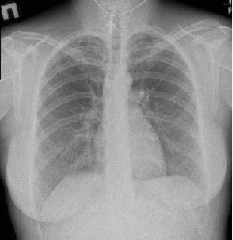

Рентгенограмма позвоночника при сколиозе

Основным способом рассмотреть строение костной ткани тел позвонков, их форму, биомеханику, является рентген-исследование. В данной статье мы рассмотрим грудной отдел позвоночника. Он состоит из 12 позвонков. Внутри них заключён костный мозг, по бокам к позвонкам крепятся задние части рёбер (передними концами они срастаются с костью грудины) всё вместе это образует грудную клетку, в которой находятся лёгкие и сердце. Также через позвоночные отверстия проходят кровеносные сосуды и нервные волокна.

Рентген грудного отдела делаться в 2-ух проекциях (в прямой и боковой), в положении лёжа. А, в случае искривления, для оценки разницы в отклонении позвоночного столба, делаются снимки в одной проекции, стоя и так же лёжа – это даёт возможность судить о стабильности или нестабильности позвоночника.

При диагностировании степени сколиоза назначается функциональная рентгенография грудного отдела. Для этого делается два снимка в прямой проекции:

- Стоя – пациент становится спиной к приёмнику рентген-аппарата, луч центрируется на среднюю область груди, делается снимок.

- Лёжа – делается так же, как и обычный снимок в прямой проекции.